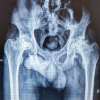

A 66-year-old female presented to our clinic with painless, limited range of motion (ROM) in her left hip, and pain in her left knee that had begun to affect her daily activities. She first noticed limitations in ROM in her early 30s and she reported that by age 40, her ROM was essentially zero. Past medical history also included bilateral knee arthritis and daily tobacco use. She reported having her hip examined as a child but did not recall receiving a formal diagnosis. Physical examination revealed increased lumbar lordosis during ambulation with compensatory hip hiking, left leg shortening with a hip internal rotation, and flexion contracture with no active and passive hip ROM. A pelvic radiograph revealed left hip fusion, severe dysplasia, and complete obliteration of the joint space (Fig. 1). Review of prior radiographs revealed arthritic changes in her left knee as well. Computed tomography (CT) reconstruction was performed to evaluate the patient’s acetabular bone stock and native femoral version, demonstrating a thinned native posterior wall and increased femoral anteversion compared to the contralateral hip (Fig. 2). The patient consented to undergo hip fusion takedown to primary THA to regain hip ROM.